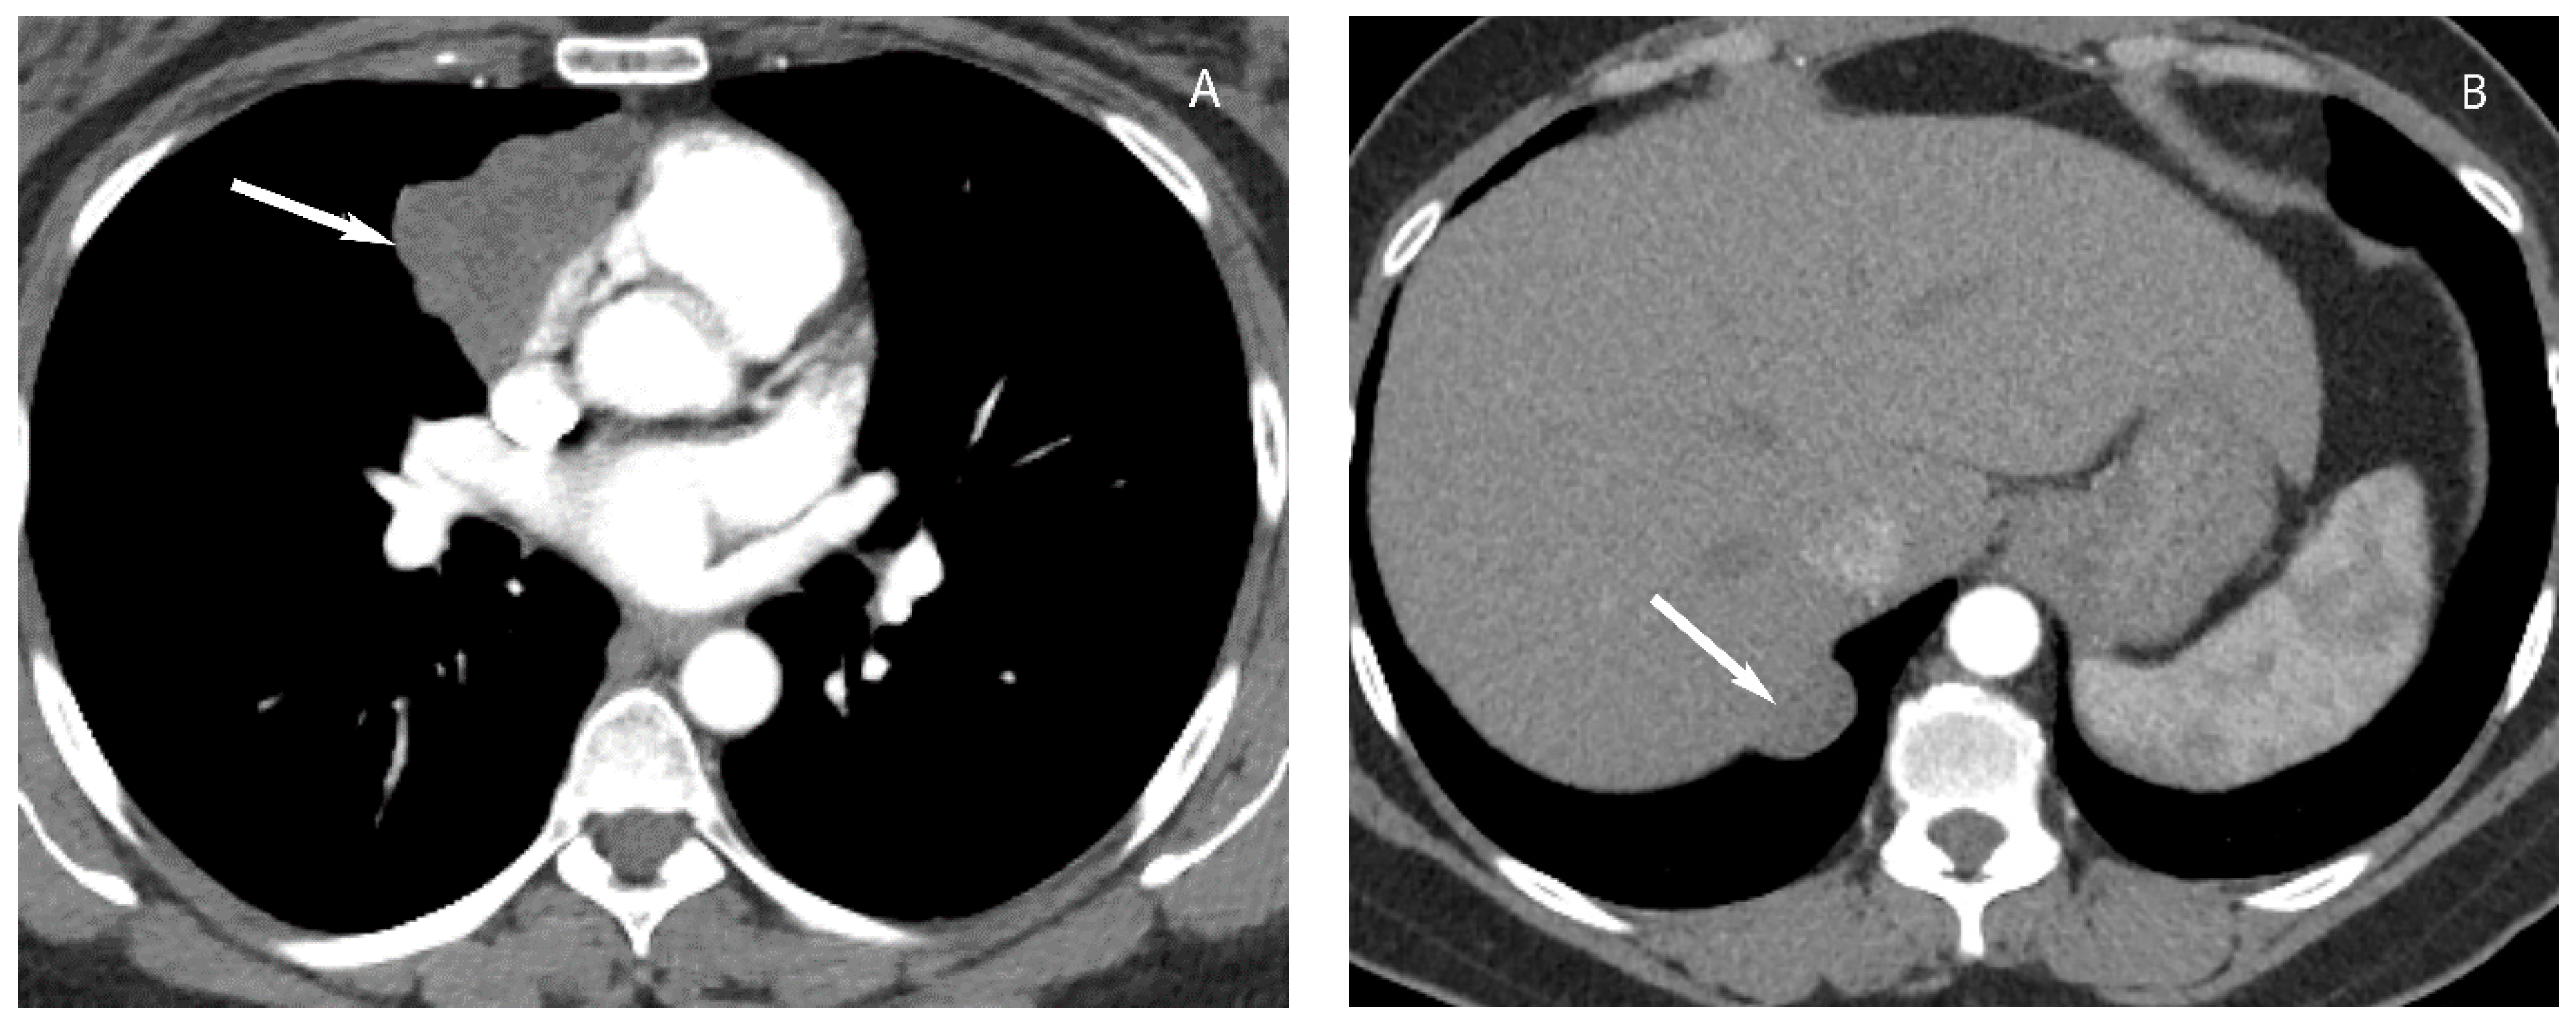

7. Germ Cell Tumors

9. Hypervascular Lesions

10. Esophageal Lesions